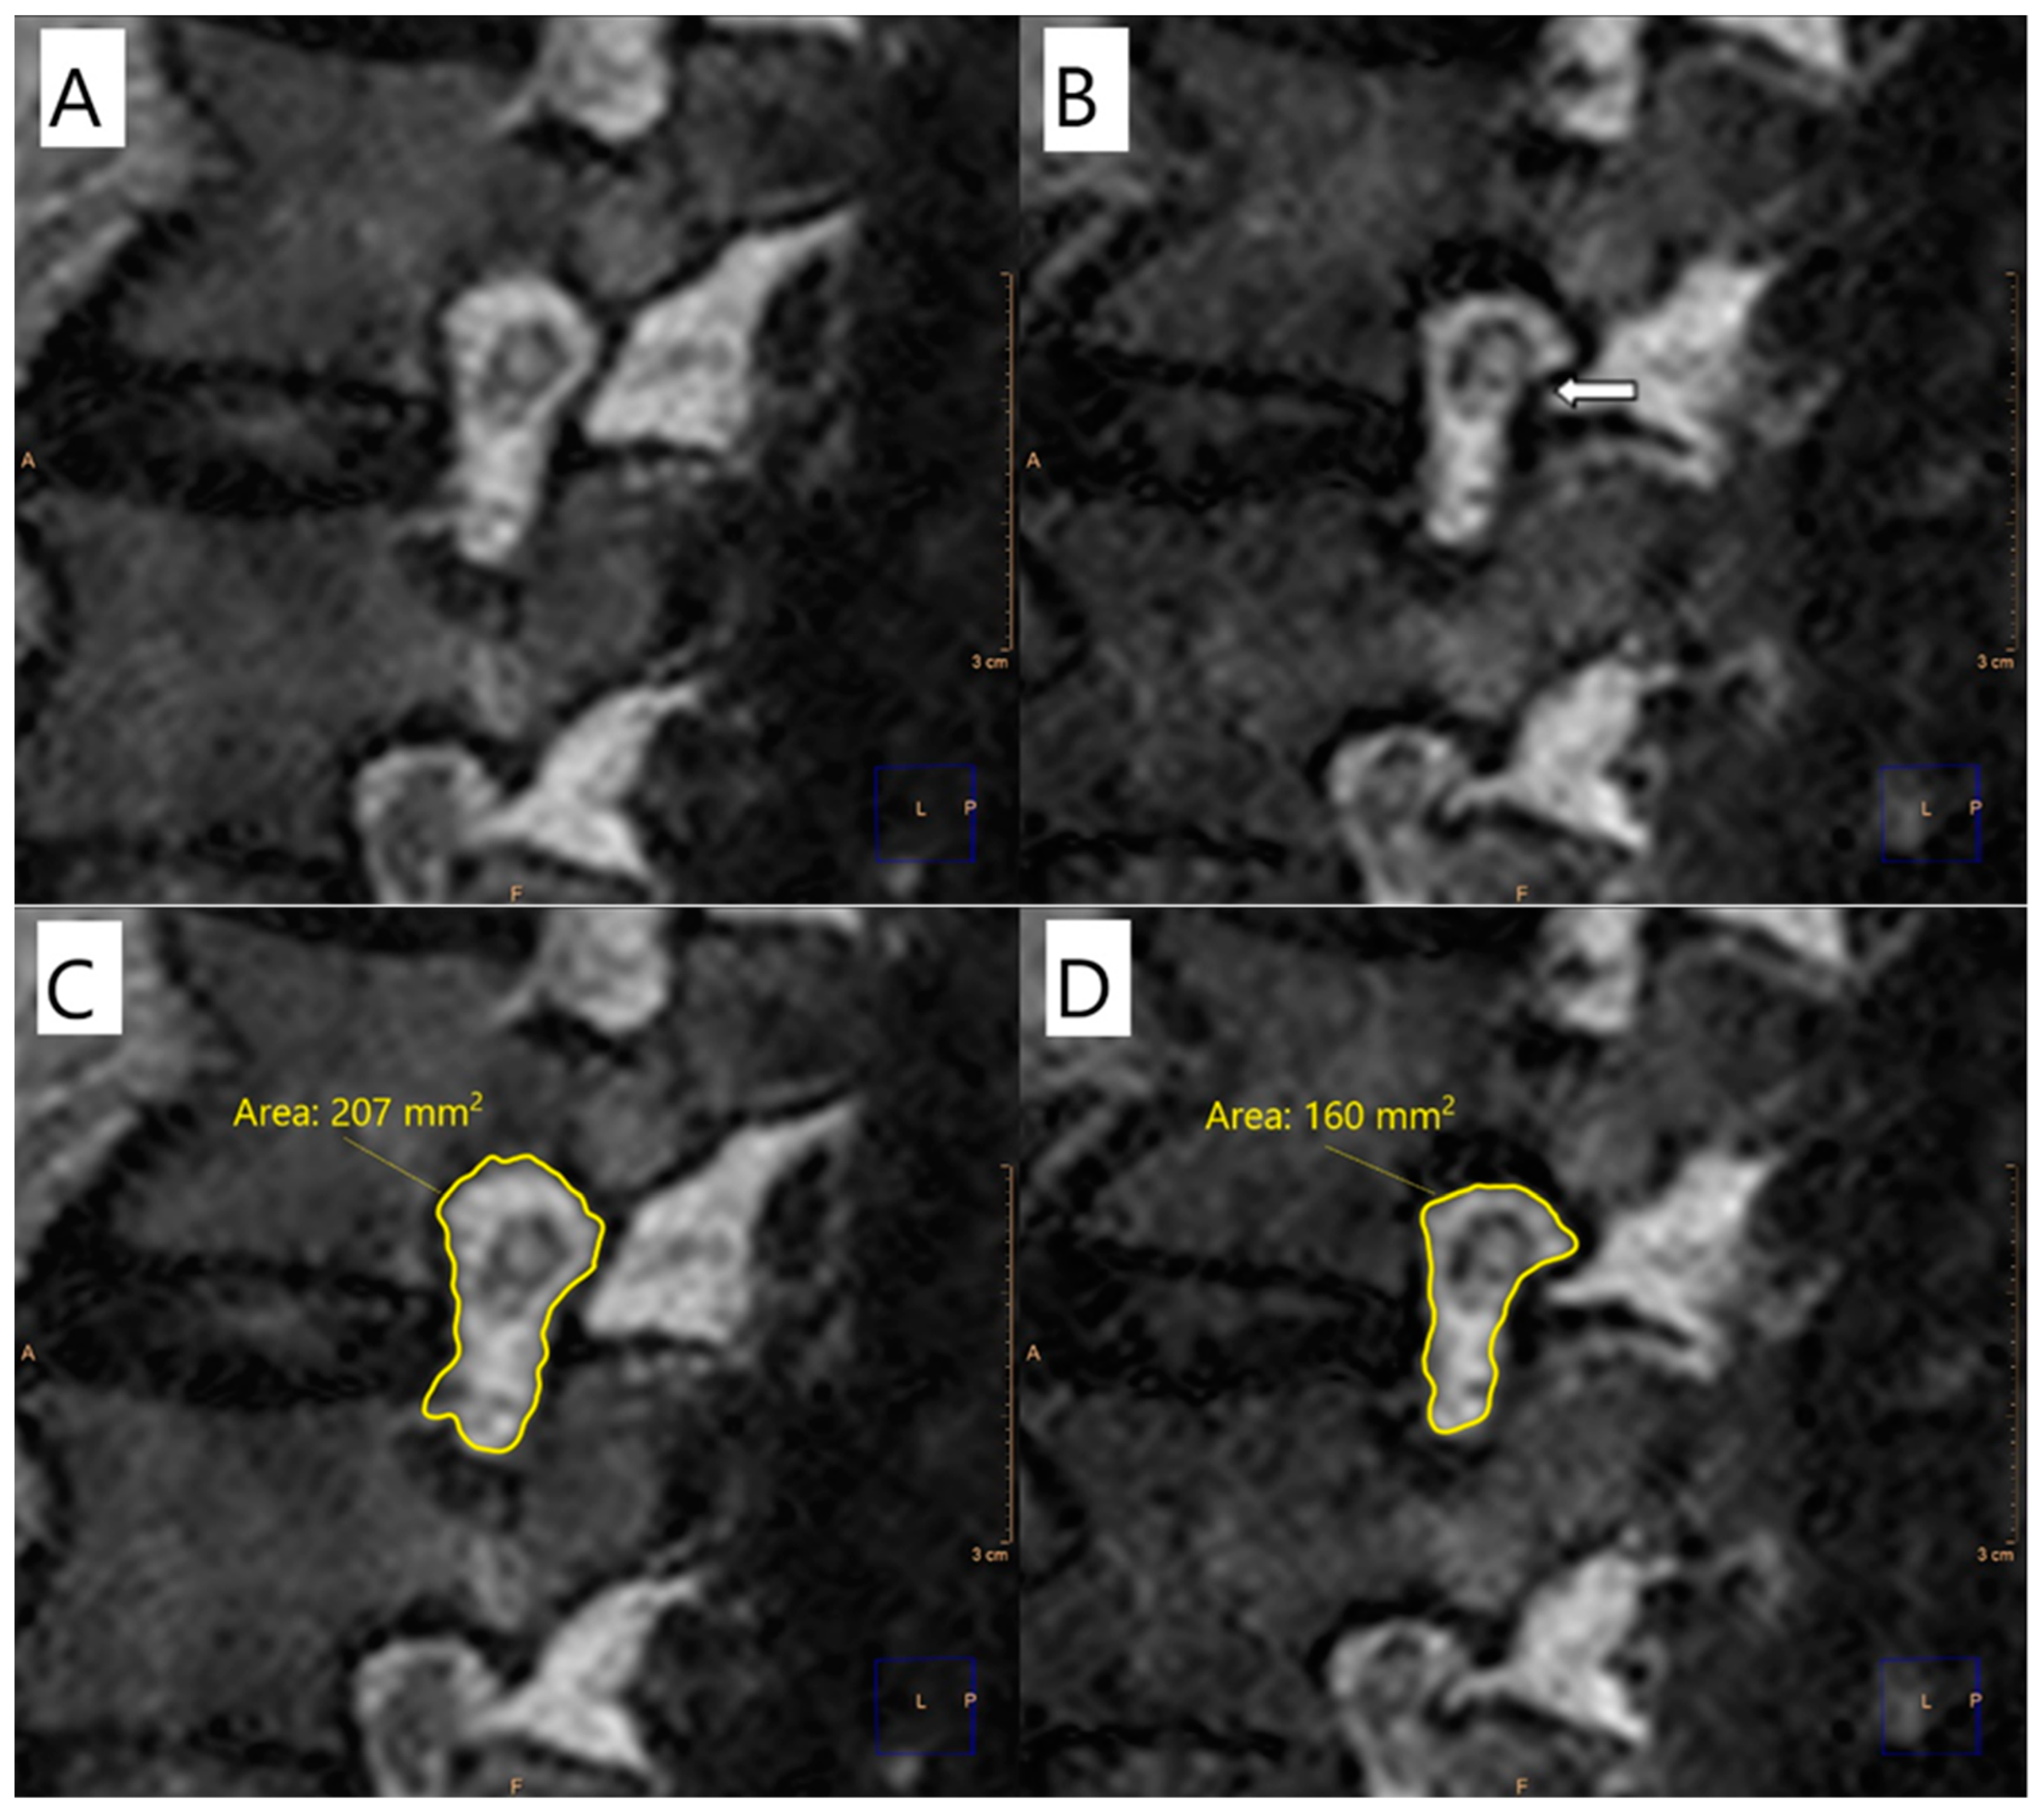

2.2. Image Analysis